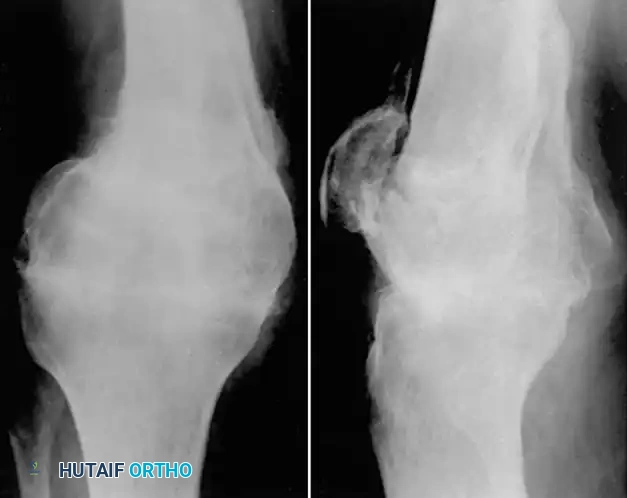

Fig. 55-16 Malunited comminuted fracture of both condyles of femur 1 year after injury. Knee motion was markedly limited and painful.

In young laborers or patients with active infection history, a compression arthrodesis is a highly durable salvage option.

Fig. 55-17 Same patient as in Figure 55-16, 3.5 months after compression arthrodesis. Knee is painless and stable for heavy labor.